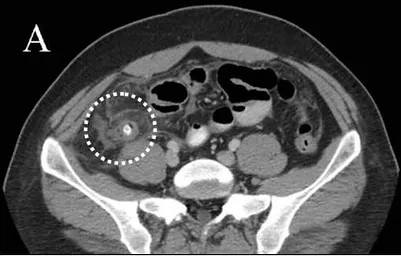

A tomografia computadorizada de abdome apresenta valores iguais ou superiores aos da ultrassonografia. O uso desse exame é limitado devido a custo, exposição à radiação e alergia ao contraste. Apresenta boa sensibilidade, pois o apêndice é mais facilmente localizado e características como aumento do seu calibre, inflamação dos tecidos a volta e presença de fecalito na base do apêndice e líquido são altamente sugestivos de apendicite aguda.

Figura 1: imagem de tomografia mostrando apêndce cecal distendido. Figua 2: imagem de tomografia mostrando fecalito na base do apêndice ceal.